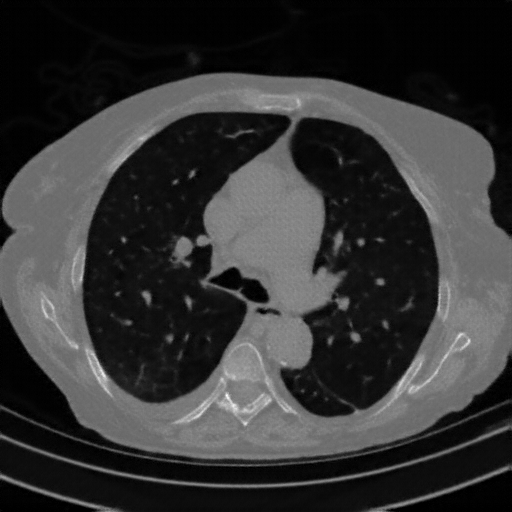

Original NATIVE CT scan (input)

Full window (WL 1023.5, WW 4095 β†’ Low βˆ’1024, High +3071)

Actual HU range: [-1024.0, 919.0]

Lung window (WL -600, WW 1500 β†’ Low βˆ’1350, High +150)

Actual HU range: [-1024.0, 150.0]

Mediastinum window (WL 40, WW 400 β†’ Low βˆ’160, High +240)

Actual HU range: [-160.0, 240.0]